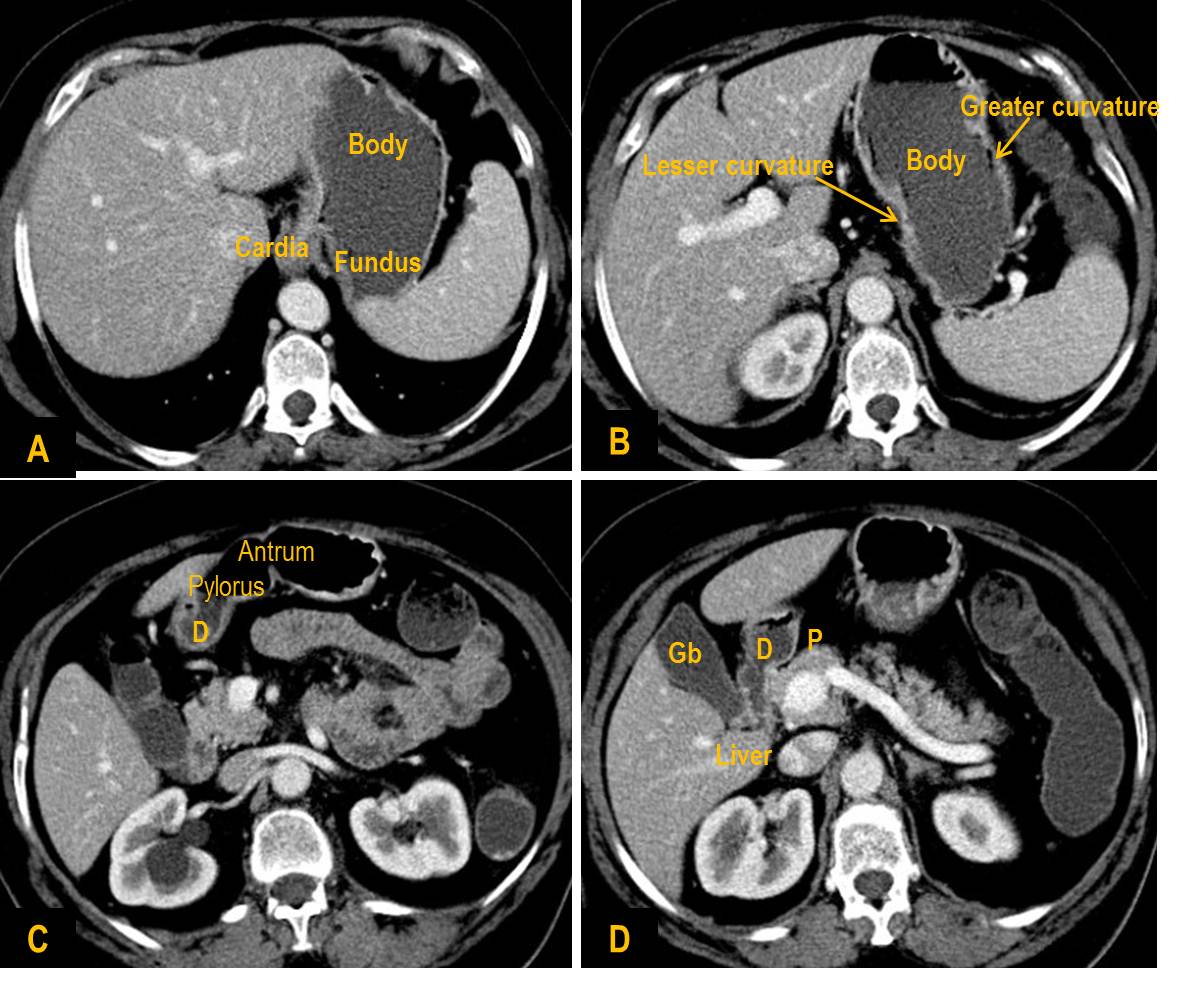

Gastric cardia radiology. Diagnostic centers of america dca is a leading diagnostic imaging facility offering a full array of imaging services in palm beach county florida. We have five state of the art radiology imaging centers in boca raton boynton beach delray beach and wellington florida. The gastric cardia is characterized on barium stud ies by three or four stellate folds that radiate to a central point at the gastro esophageal junction also known as the cardiac rosette fig 2 12. Variations and benign influences may closely resemble the more dangerous lesion.

Cain jc jordan gl jr comfort mw gray hk. J am med assoc. The gas tric fundus is dened as the portion of the stomach craniad to the gastric car dia. Commonly accompanying this are abnormally dilated short gastric veins which pass from the splenic vein to encircle the gastric fundus and form gastric fundal varices.